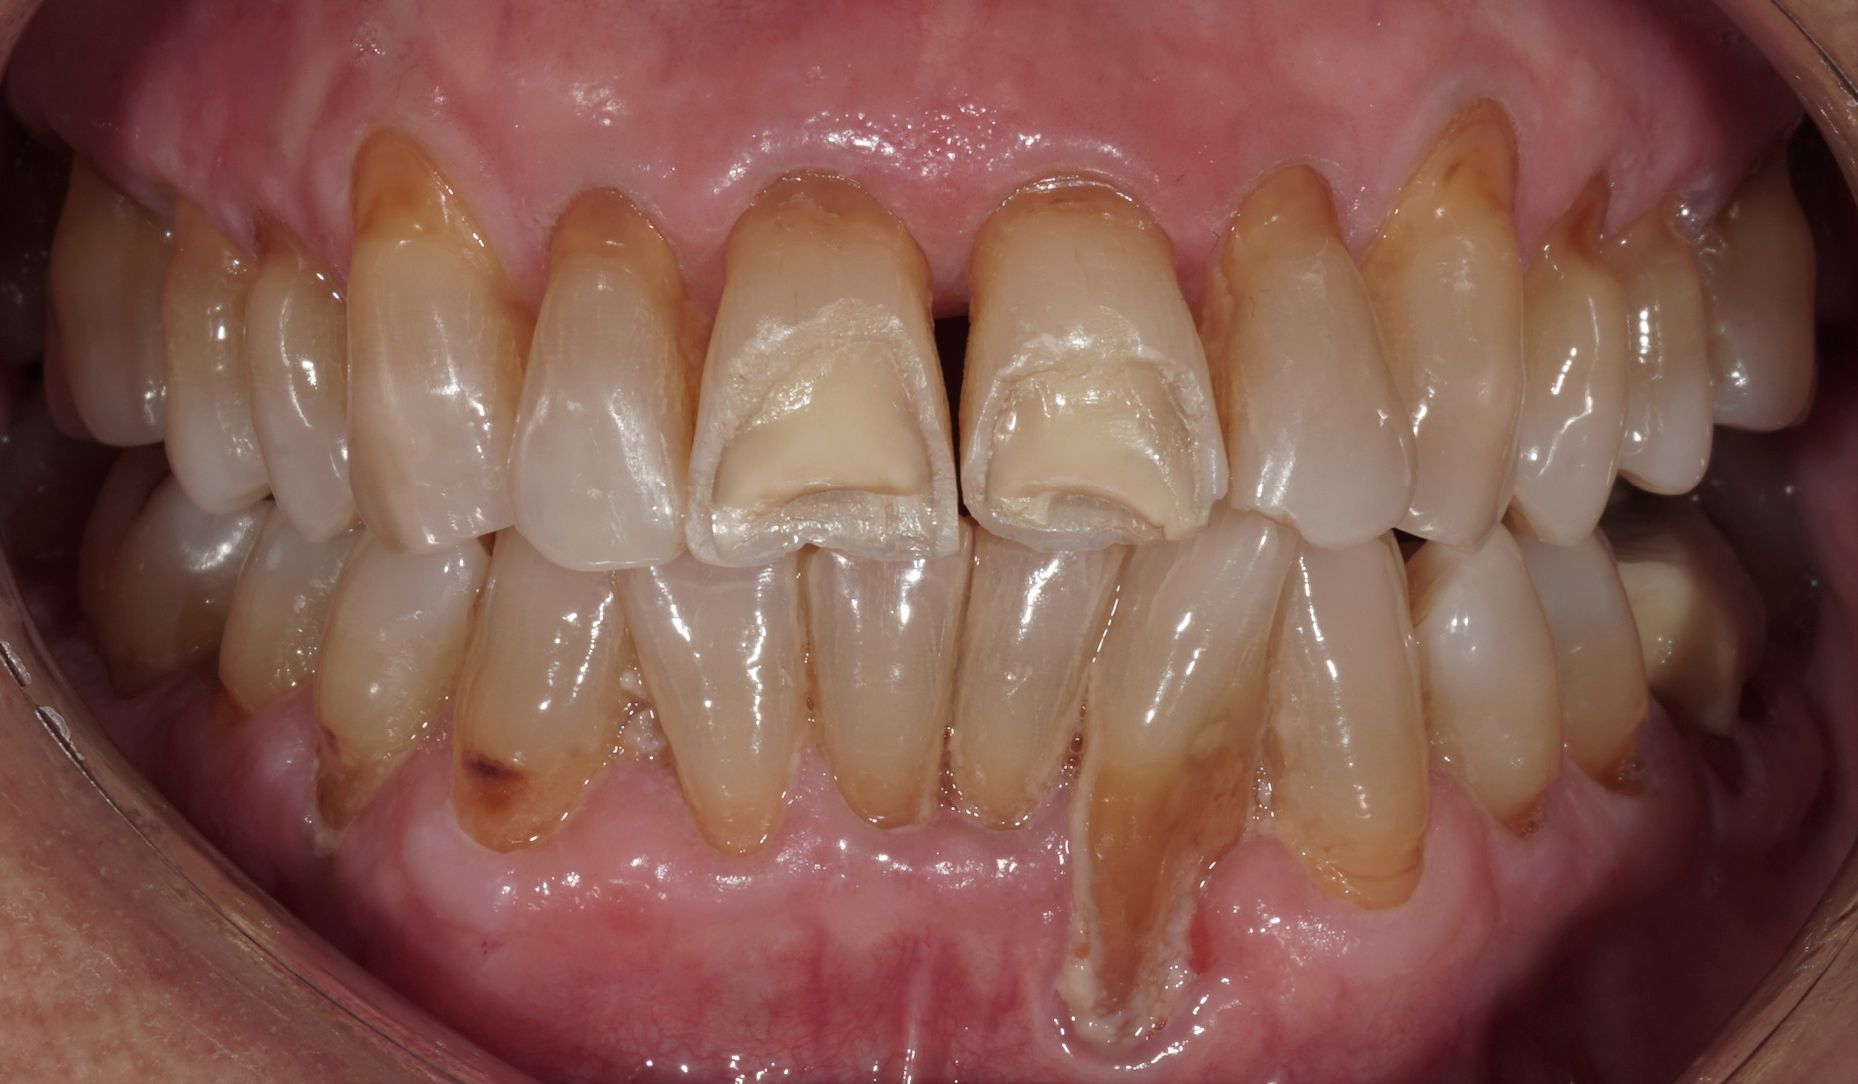

Ryc. 2. Stan kliniczny podczas pierwszej wizyty wgabinecie stomatologicznym.

Ryc. 3. Zgryz otwarty w lewym, tylnym obszarze żuchwy.